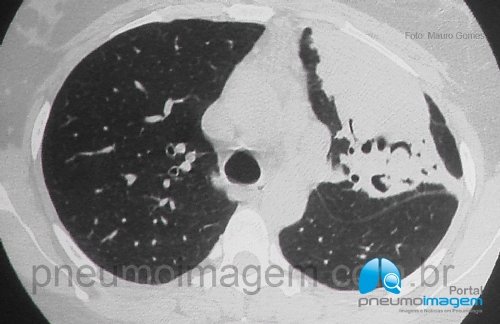

CASO CLÍNICO #47Essa doença muitas vezes é confundida como sendo uma micose, pois o nome dela e do seu agente etiológico é muito parecido com fungo. Você sabe qual é essa doença? Deixe os seus comentários abaixo!

This disease is often confused as being a fungal disease, because the name of it and its etiological agent is similar to fungus. Do you know what this disease is? Write your comments below!